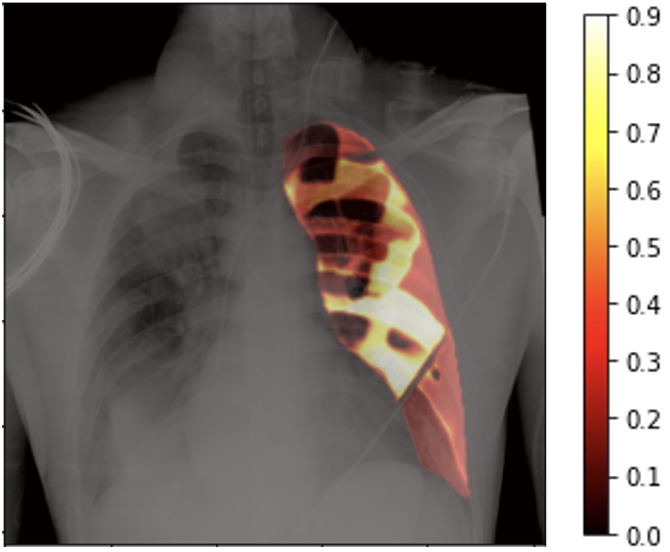

Figure 1: Heat-map of Dice values obtained by placing the prompt at various locations in the lung.

Figure 1 shows the overlay of a chest X-ray image and the heat-map of Dice values when the prompt is placed at different locations of the lung region. The large diversity of Dice values (0.2 to 0.9) highlights that given a click prompt inside the lung region of an X-ray image, it is plausible that another location provides a more accurate segmentation.

Since X-ray is a summative modality, the intensity values under the lung mask are a result of superimposition of soft tissue, ribs, cardiac region, and occasional extraneous objects such as PICC lines. Though visually the lung region may appear equally dark in X-ray images to the user, it is not homogeneous, and its heterogeneity is further amplified by the presence of pathology.